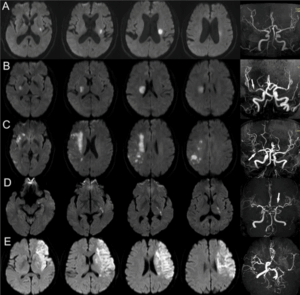

Thank you for reading this post, don't forget to subscribe!- 緊急磁力共振MRI造影對於在中風黃金小時內進行準確診斷至關重要,尤其是對於缺血性中風。

- MRI 可提供腦部及其血管的詳細影像,從而評估中風類型。

- MRI 亦可顯示缺血性中風時血管阻塞的部位和範圍,或出血性中風時出血的部位和範圍,從而提供選擇合適治療方案的指導。

全天候24小時 (24/7) 緊急磁力共振MRI造影,快速診斷急性中風

- 在香港腦脊中風及痛症狀顧問中心,我們提供全天候24小時 (24/7) 緊急磁力共振MRI造影服務,可在中風症狀出現時提供快速準確的診斷。

- 及時進行 MRI 中風診斷,以便在黃金小時內及時有效治療,拯救大腦,減少長期殘疾並改善復康效果。